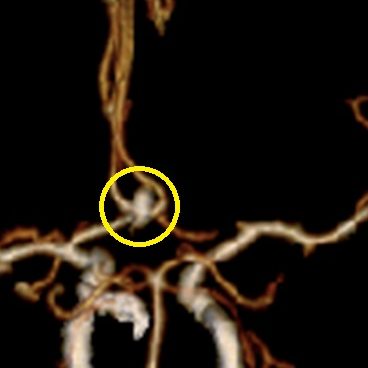

当科で治療した年々大きくなった大型脳底動脈瘤の3次元脳血管撮影像です。脳動脈瘤と周囲の血管の状態が非常によく分かるため、術前に十分な検討が可能でした。

術前

術後、脳底動脈瘤はコイルにより完全に塞栓され、正常の脳底動脈の血流は維持されている。